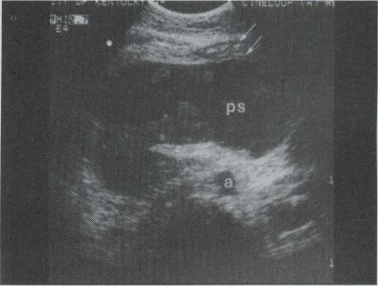

46.患者男25岁,转移性右下腹痛1天,体检:右下腹叩击痛及反跳痛(+),血WBC1.3万,中性粒细胞82%,B超检查声像图如图所示,根据超声声像图,诊断为()